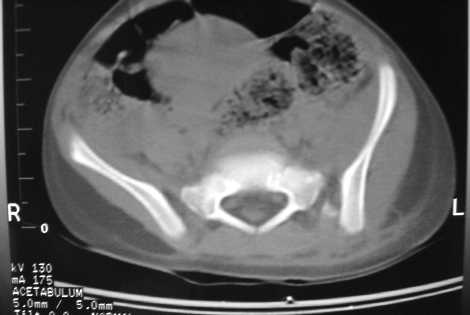

A 3 y-old girl, injured by after a traffic accident, no other skeletal and organ injuries. She was in skeletal traction now and initial, after skeletal traction AP views and CT scans of the pelvis were attached.

I have had two pediatric pelvic ring disruptions wth dislocation of the SI joint as in your case. A 4 year old and a 7 year old. I found that open reduction, as recommended by Tile, was needed in both with 4.5 mm cannulated iliosacral screws.